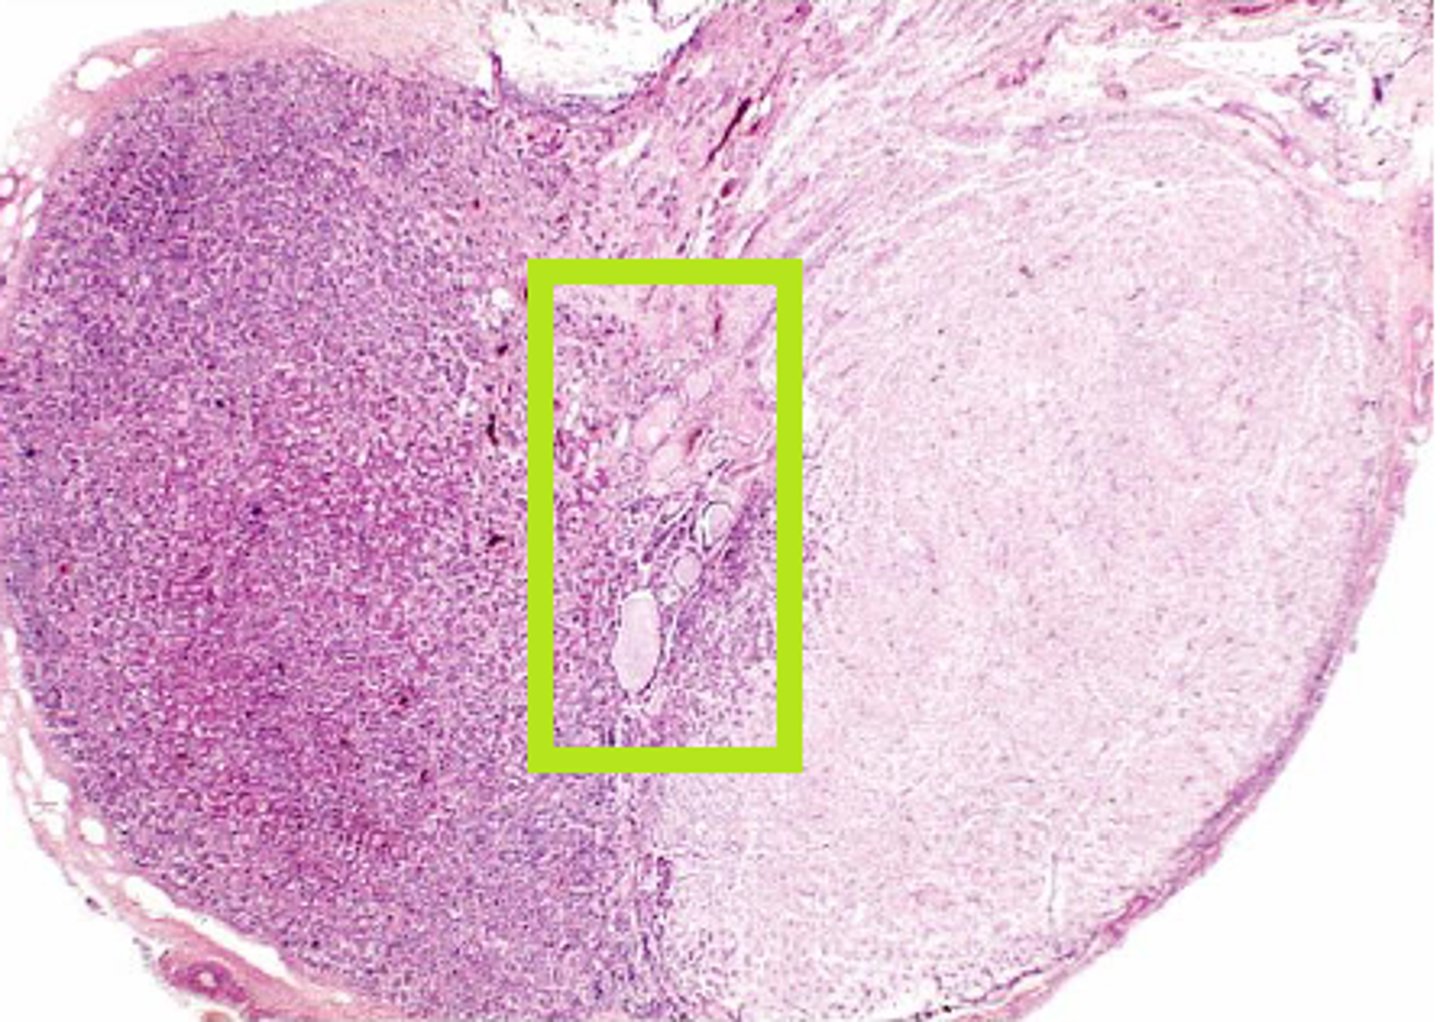

pituitary adenoma

gross pathology of _______ _________

-tan-to purple in color and creamy in texture

-macro or micro

histology of _______ _________

-uniform, polygonal cells arranged in thin cords and ribbons; monotonous appearance of small round cells

-see acidophils, basophils, and chromophobes

Psammoma bodies

distinct histological finding of prolactinomas

prolactinomas

electron microscopy findings of _______:

-abundant rough ER, prominent golgi complel, but sparse secretory granules